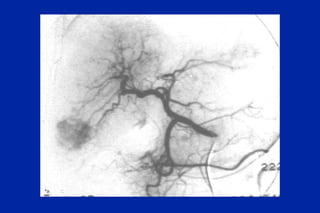

Este documento resume los principales tipos y técnicas de angiografía. Describe brevemente la angiografía, arteriografía, flebografía y linfografía, así como las técnicas de contraste y materiales utilizados. También explica los principales accesos vasculares, la técnica de Seldinger, la angiografía por sustracción digital y algunas técnicas endovasculares comunes.